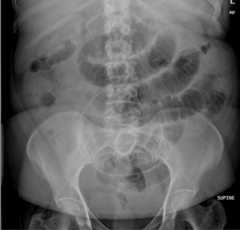

Plain abdominal radiography of patient 2

Plain abdominal X-ray of a patient showing distension of the large bowel and gas-fluid levels as signs of a large bowel obstruction (LBO)

Image: “Plain abdominal radiography of patient 2” by Department of General, Visceral, Vascular and Transplant-Surgery, Julius-Maximilians-University of Würzburg Würzburg Germany. License:CC BY 3.0